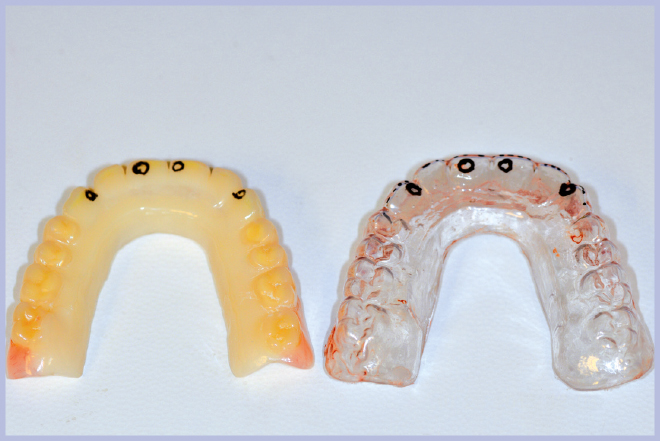

Quindi, con l’ausilio di una mascherina in resina trasparente, si è effettuata la registrazione occlusale; la mascherina è stata sfruttata anche per la demarcazione dei punti della nuova protesi da scartare in corrispondenza della posizione delle cappette (Figg. 7, 8).

La nuova protesi, realizzata in materiale composito sul modello di quella pre-esistente (Fig. 9), è stata poi ribasata in bocca sull’armatura di rinforzo fissata ai monconi (Fig. 10). Ad indurimento avvenuto della resina per ribasature, si sono rimosse le viti e si è rifinita la protesi. L’operazione di rifinitura da parte del tecnico è di grande importanza, perché si deve il più possibile ridurre l’estensione della flangia vestibolare al fine di favorire una buona detersione da parte del paziente.

- Fig. 7 – Mascherina in resina per la registrazione occlusale

- Fig. 8 – Demarcazione della posizione delle cappette sia sulla mascherina che sulla nuova protesi

- Fig. 9 – Protesi nuova in composito